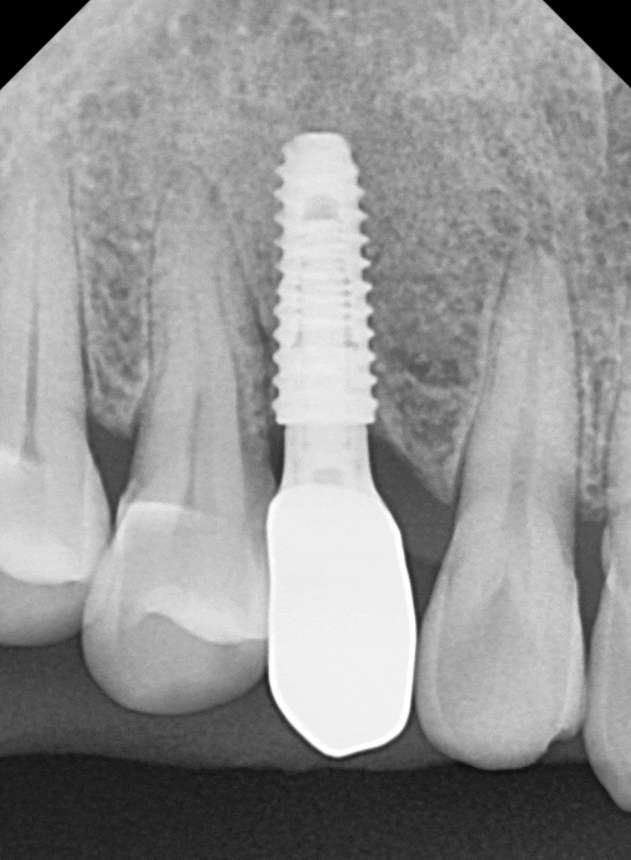

엑스레이를 찍어보니

아주 짧고 가느다란 유치 뿌리가 보입니다.

일반적인 송곳니들은

다른 치아들에 비해 뿌리가 긴 편인데,

유치는 영구치에 비해

상대적으로 뿌리가 짧다보니,

사용할 수 있는 기간이 더 짧을 수 밖에 없어요.

더 큰 문제는 3D CT 상에서

뿌리 끝에 염증이 발견되었다는 점인데요.

뿌리 끝에 이미 염증이 생겨 있었고,

그 염증 때문에 주변 잇몸뼈가 녹아내려

뿌리 끝자락만 간신히 뼈에 걸쳐져 있는 상태였어요.

251126

이대로 두면 염증이 옆에 있는

건강한 영구치들의 뼈까지 녹일 수 있는 상황이라,